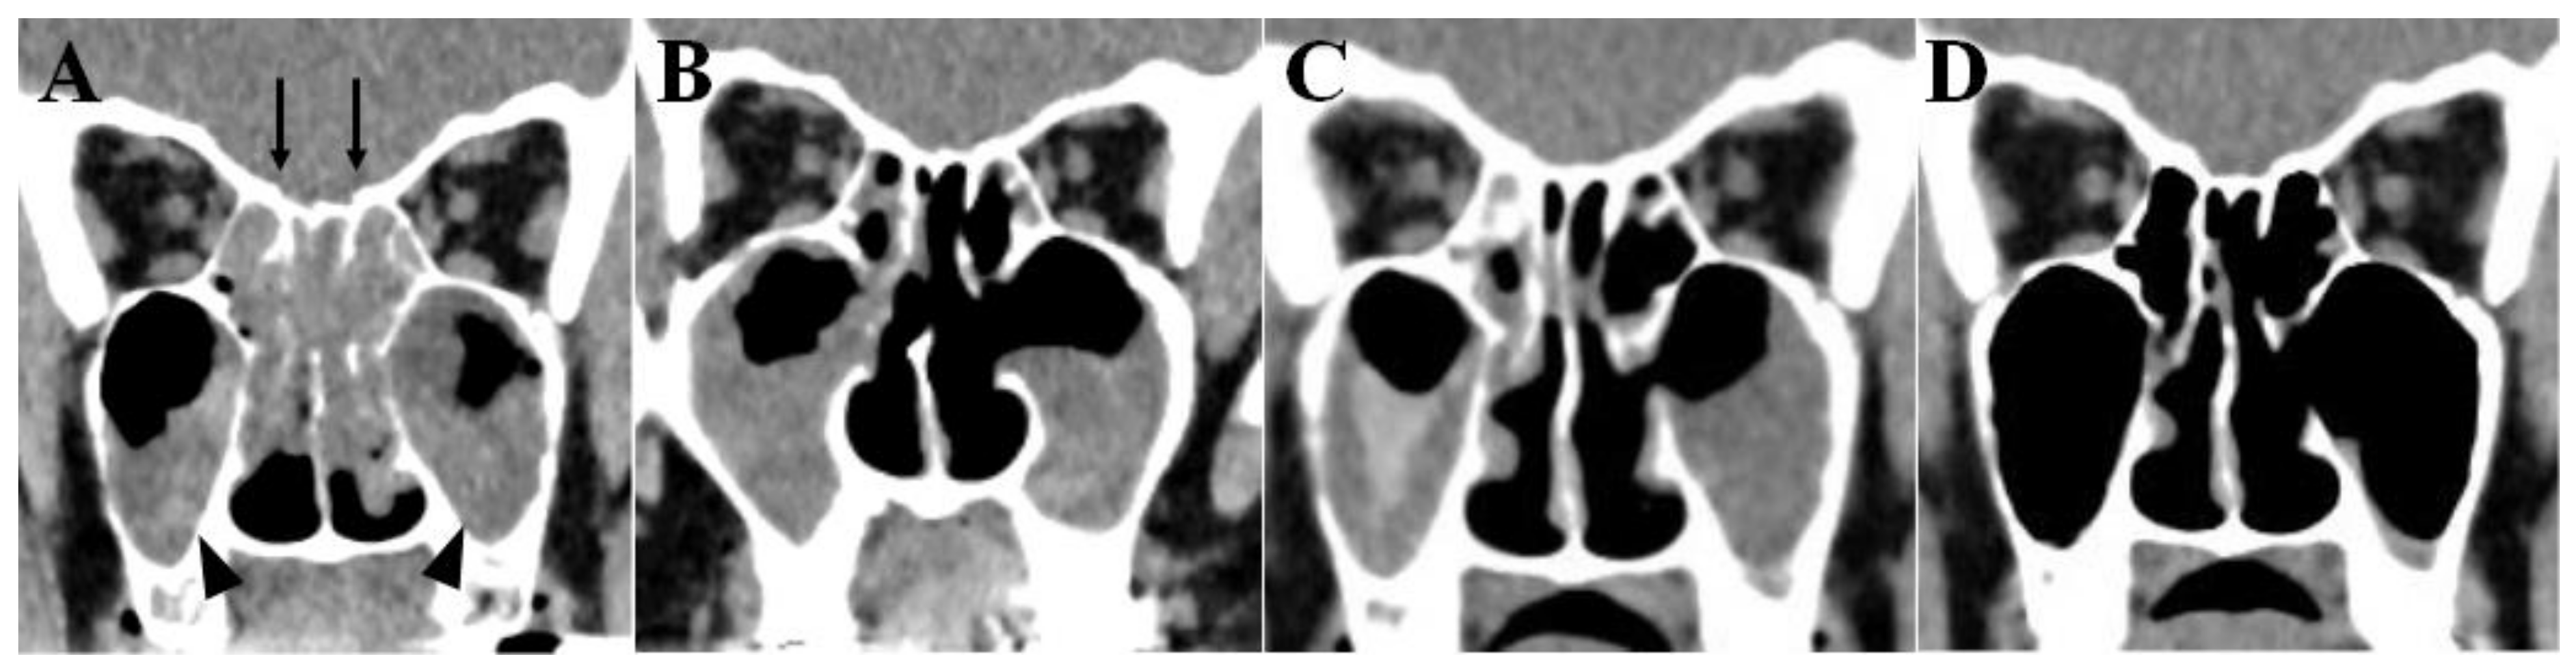

2. Case Presentation